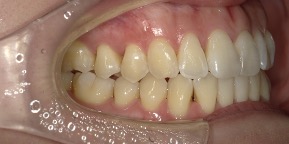

26歳女性のビフォーアフター

| 診断 | 空隙,叢生 |

| 治療方針 | 治療方針:前歯の咬合関係改善と空隙閉鎖を主な目的にて主にIPR(歯と歯の間をわずかに削合してスペースを獲得する方法)を組み込んだ動的矯正治療を行い、空隙、前歯咬合を改善後、保定を行う。臼歯部の咬合関係はプランの都合上維持することとした |

| 治療費 ※ | 69万8千円(診断、型取り、矯正中のメンテナンス、保定装置を含む料金) |

| 治療期間 | 1年8か月 |

| リスク | 1日20時間以上マウスピースを使用できない場合、歯が動かなかったり、想定しない誤差により不完全に終わる可能性がある。装着時や食事時に痛みを伴う。歯肉退縮や虫歯になるおそれがある。また、指導通りに装着できていない場合や適切なブラッシングが出来ていないとそのリスクが高くなる。歯根が短くなることがある。ごくまれに歯の神経が損傷してしまうことがある。過去にぶつけたり深い虫歯治療をしたことがあるとそのリスクはやや高くなる。矯正後には保定装置が必要。適切な使用ができない場合、後戻りの原因となる。将来的に歯並びが動いて再矯正が必要な場合がある。舌癖(舌で歯を押し出す癖)親知らずが正常に生えていない場合、その可能性がやや高くなる。 |